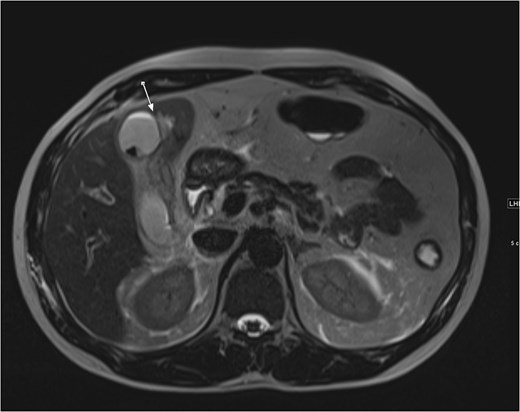

An ultrasound of the abdomen showed an impacted stone at the neck of the gallbladder with acute cholecystitis. The patient was admitted and started on IV antibiotics. He developed tachycardia reaching 110 bpm and had a high white blood cell count; therefore, the decision was made to proceed with a contrast-enhanced computed tomography (CT) scan, which showed evidence of acute cholecystitis and left PVT (Fig. 1). The medical team was consulted, and IV heparin without bolus was started. The gastroenterology team was consulted for his high bilirubin levels and advised for magnetic resonance cholangiopancreatography (MRCP), which was done the next day and confirmed the findings of left PVT (Fig. 2). MRCP also showed a micro perforation of the gallbladder and no biliary obstruction or stones (Fig. 3).

MRCP T1-weighted images: (A) axial cut; (B) coronal cut. Arrow indicates left portal vein thrombosis.